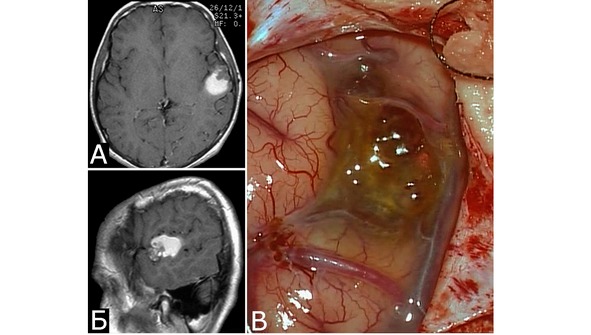

Кавернозные мальформации имеют характерный вид, который трудно спутать с каким-либо другим видом патологии. Они представляют собой округлые образования красно-синюшного или бурого цвета, с неровной, бугристой поверхностью, четко отграниченной от окружающей ткани (рис. 7).

Рис. 7. Вид каверномы на операции в процессе выделения (А) и после удаления единым блоком (Б)

Ткани, окружающие каверному, чаще всего грубо изменены. Типична желтая окраска мозгового вещества, мозговых оболочек или нервов, свидетельствующая о перенесенных кровоизлияниях (рис. 8). Этот признак помогает обнаружить каверному в ходе хирургического вмешательства.

Рис. 8. Б-ной И-юн, 13 лет. Кавернозная мальформация и гематома оперкулярной зоны слева. Повторные кровоизлияния. А, Б – МРТ, режим Т1, аксиальная и сагиттальная проекции. 4-е сутки после 2-го кровоизлияния. Видна ткань КМ в виде гетерогенного сигнала, и гематома в виде гиперинтенсивного сигнала, расположенная кзади от КМ. В – интраоперационное фото после вскрытия ТМО, 2 месяца после 2-го кровоизлияния. Виднаи желтая окраска окружающих тканей и отдельные каверны, выходящие на поверхность мозга